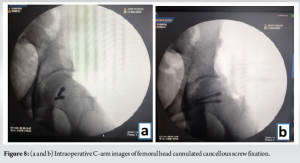

On 10th day post-trauma, the patient positioned in right lateral position, using Kocher-Langenbeck approach, the patient underwent left head of femur open reduction internal fixation with 2 headless compression screws, and posterior acetabular wall fracture was reconstructed using Ethibond. The choice of a posterior approach was chosen in view of initial presentation following injury being posterior, the tear of the capsular and muscular structures allows direct access to the joint and following fixation, and the torn structures can be visualized and repaired. The only limitation of achieving absolute reduction is to deliver the remaining portion of the infrafoveal femoral head to the rest of the femoral head and proximal femur, thereby gaining the necessary trajectory for screw fixation. This was achieved by dislocating the femur and accessing the infrafoveal fragment through the inferior portion of the joint and then reducing the fracture with a reduction clamp and provisional fixation was done with two 2 mm Kirschner wires, following which headless compression screw was inserted and maximum compression was achieved in-between the fragments (Fig. 8). The hip was relocated, the capsule was repaired with Ethibond, and the torn external rotators were reconstructed. Using image intensifier, it was confirmed that the joint was congruous; clinical assessment under anesthesia was performed and there was no impedance or blockade throughout the complete range of movements in all planes. To reduce the morbidity and the risk of arthrofibrosis of the knee, PCL reconstruction was planned for at a later date. Post-operative X-ray was done on post-operative day 2 which showed excellent reduction and articular congruity (Fig. 9).

At 3-month follow-up postoperatively, he was able to mobilize full weight bearing without support and achieved a knee range of motion of 0–120°. At 18-month follow-up, the patient presented to the outpatient department with minimal hip and knee discomfort. He was able to carry out his daily activities without hindrance and able to sit on the floor crossed leg (Fig. 10). He was able to achieve a hip abduction 0–40°, hip extension 0–20°, hip flexion of 0–80°, and knee flexion 0–130° (Fig. 10). He had no knee instability and anterior drawer, posterior drawer, varus stress, valgus stress were negative. Conservative management for the left knee was decided after considering the patient’s current clinical condition and stability of the knee. Radiography of the hip and knee revealed concentric reduction of hip and knee without any evidence of avascular necrosis of the femoral head.